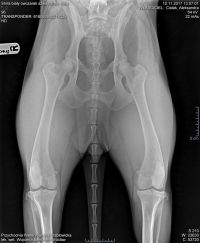

Badania HD A i ED 0/0

Dziś już oficjalnie możemy się pochwalić, rewelacyjnym wynikiem:

Dysplazja stawów biodrowych - wolna od dysplazji HD A

Dysplazja stawów łokciowych - wolna od dysplazji ED 0/0

VICTORY VANILLA of Alpen Angel HD A, ED 0/0

Z radością informuję o wynikach badań VICTORY VANILLA of Alpen Angel : HD A, ED 0/0